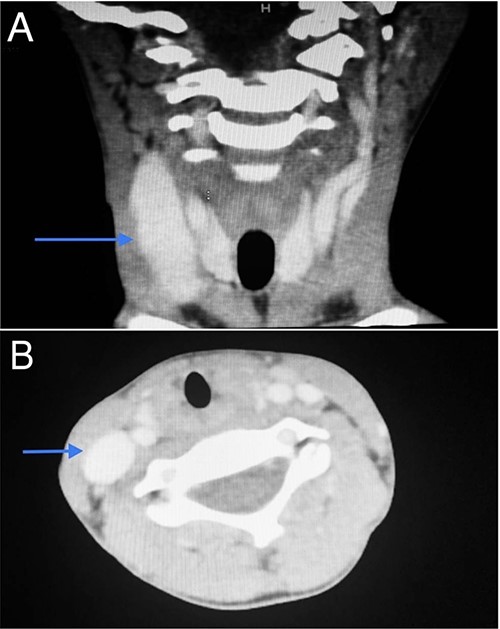

Imaging examination of the patient was done by performing CT and US. US Doppler showed a right dilated internal jugular vein (Fig. 2). The CT scan confirmed this finding, which suggested internal jugular vein phlebectasia (Fig. 3).

CT scan of the first patient in coronal view (A) and axial view (B) with blue indicate internal jugular phlebectasia.